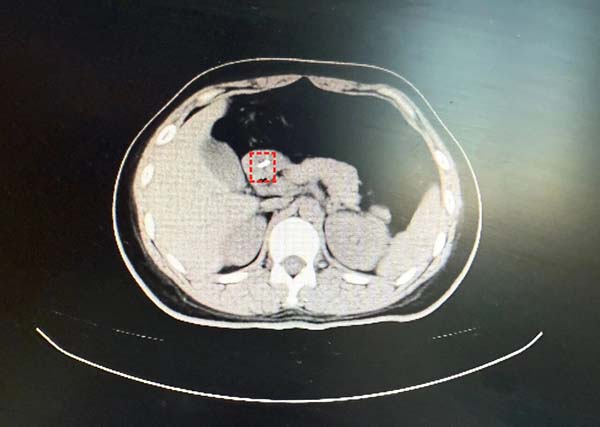

患者付某,女性,27岁,因“不慎吞食异物40分钟”于2025年12月23日18:04至中国中医科学院望京医院急诊外科就诊。患者无明显胸痛、腹痛、咽痛等不适。上腹、下腹、盆腔CT平扫:胃窦腔内细条形金属样高密度影,结合病史,考虑异物可能性大。与患者及家属充分沟通病情、交代内镜操作相关风险并获知情同意后,消化科牛然副主任医师带领内镜团队迅速为患者施行内镜下消化道异物取出术。镜下所见:进镜至十二指肠水平段时,于肠腔内探及一枚长约2厘米的金属细钉。该异物位置较深、形态细长,有坎顿、出血或穿孔的风险。幸运的是异物钳配合透明帽取出,过程顺利,所经过消化道粘膜观察无破损及划伤,患者无不适症状。

十二指肠水平部发现异物